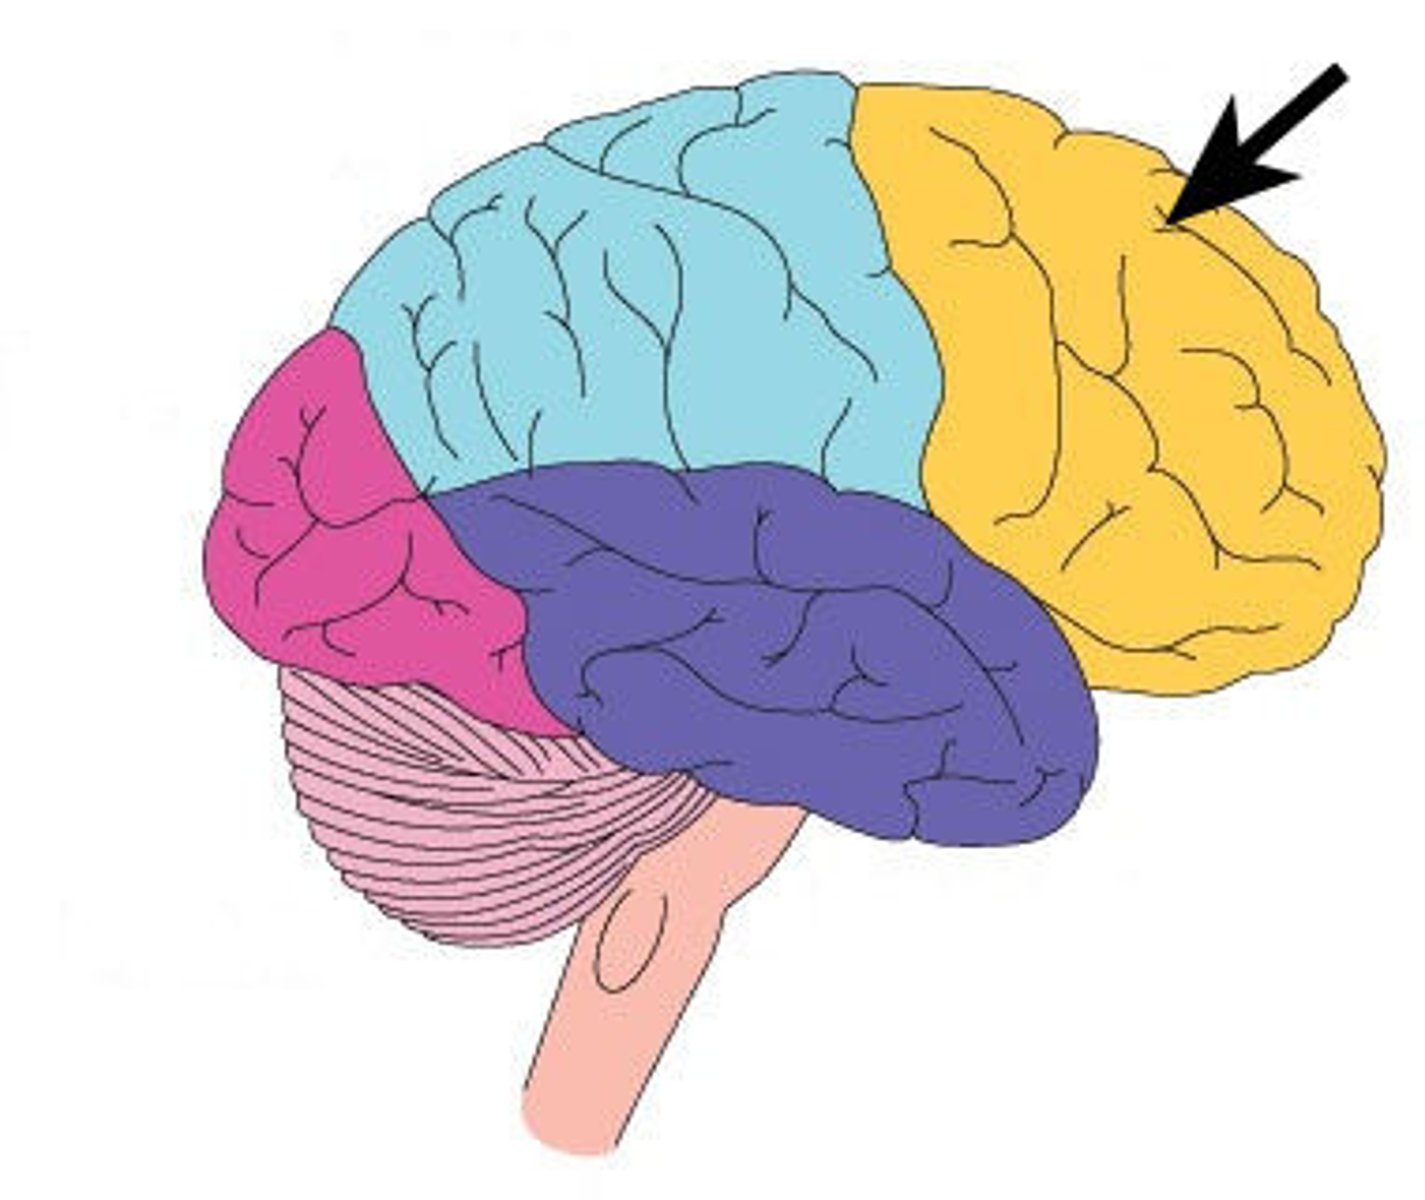

Occipital Lobe

What is this lobe?